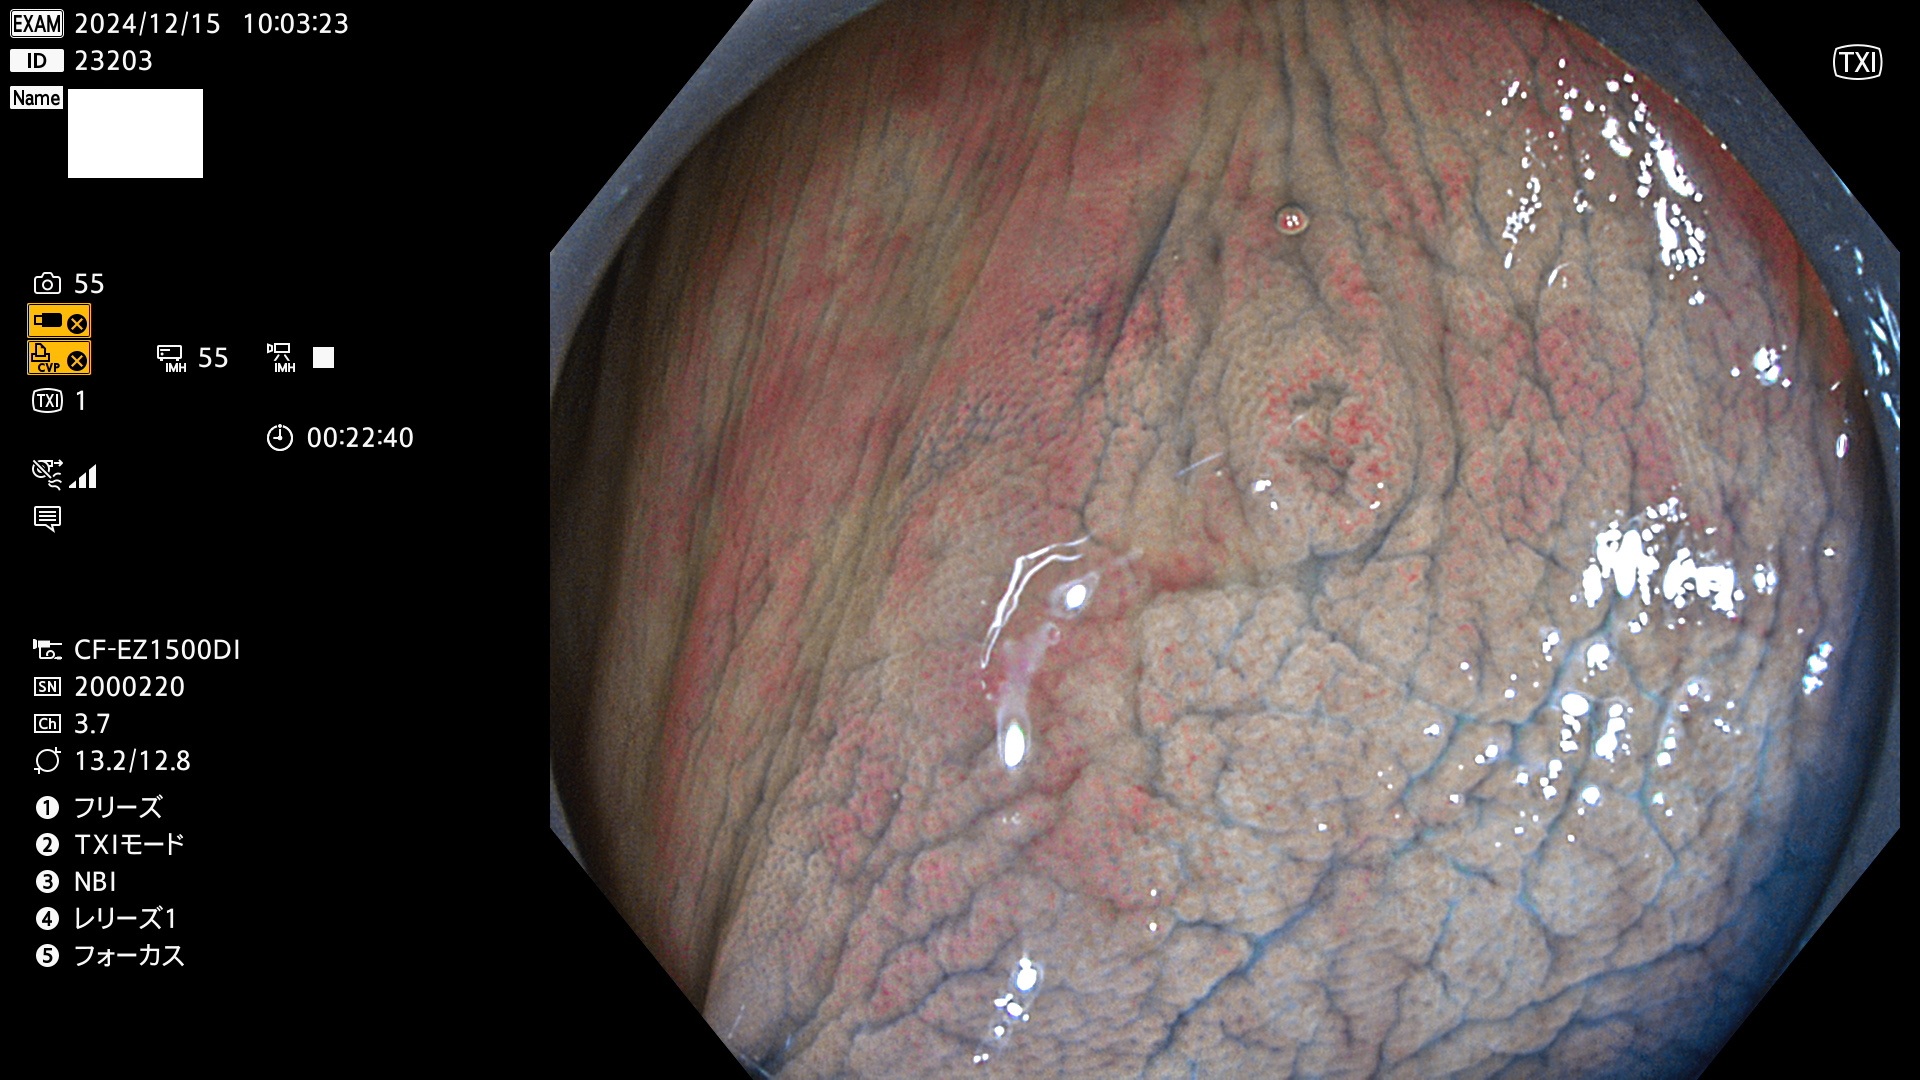

完全に平坦な物をUb、陥凹している物をUcと呼びます。最も発見が難しく危険な病変です。

毎週の検査(木・金・土・日)に発見されたUb、Uc型・腺腫を、その週の日曜の夜にUPし1週間、提示します。

抽出の対象期間 2024年12月12日〜12月16日の5日間(60件の検査)13件 (13/60=21%)